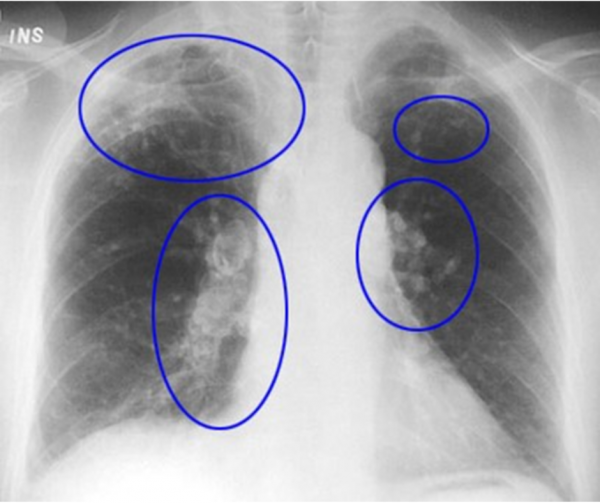

Lung Disease, Xray Photograph by Science Photo Library Woodworking And Lung Disease  if you work with hardwood, softwood or wood composite boards, you are likely to be exposed to wood dust. Approximately 3.6 million workers in the european union are exposed to wood dust 1. Increasing evidence suggests that idiopathic pulmonary fibrosis (ipf) occurs more often in subjects previously.  exposure to wood dust can cause inflammation and irritation of the. Woodworking And Lung Disease.